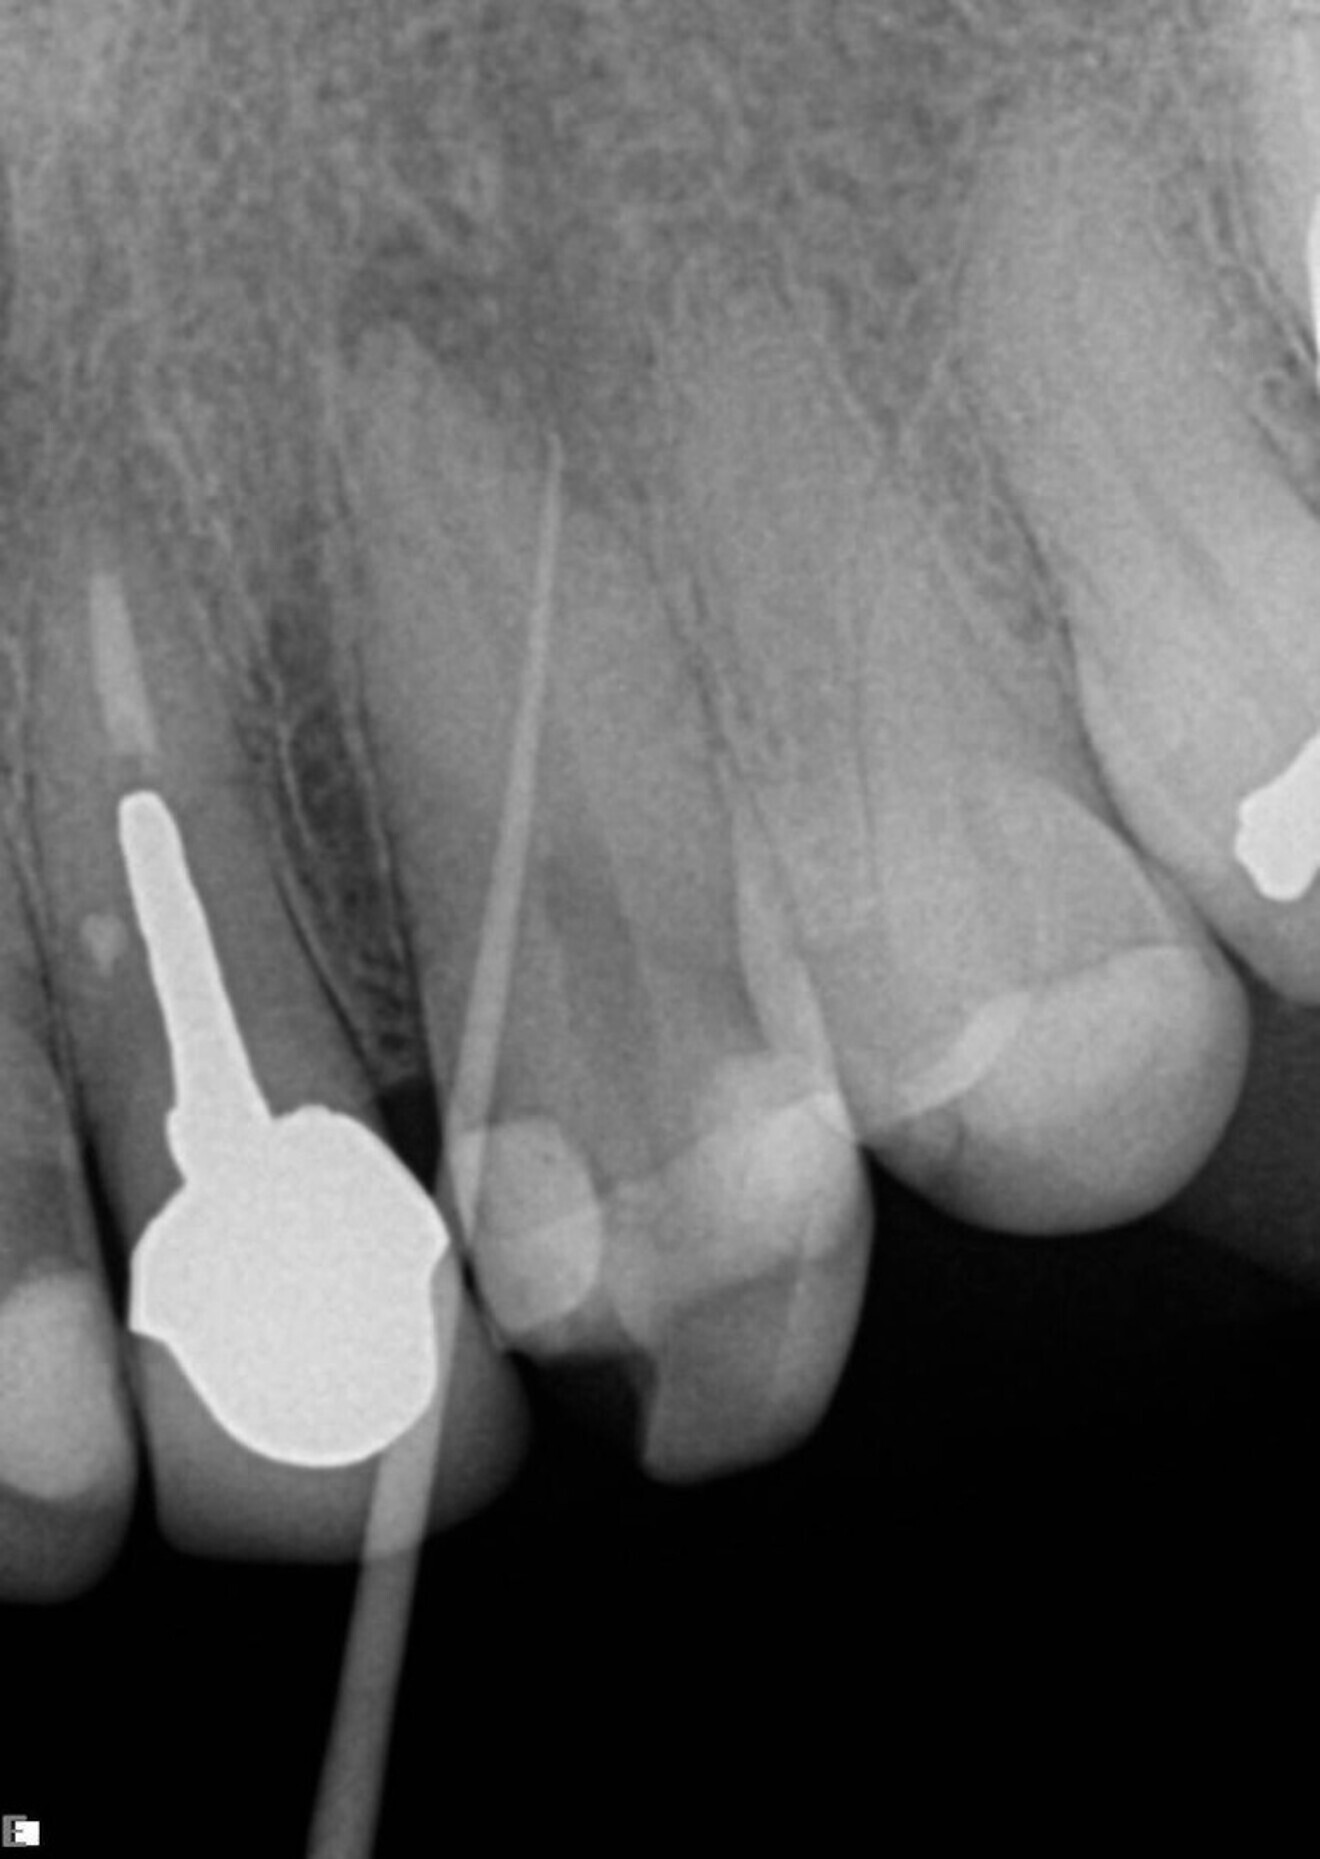

The next example was also a straightforward case. This was a maxillary lateral incisor with a necrotic pulp and a slightly resorbed apex. A 55/0.06 ZenFlex file was used in a single-file technique to treat this canal (Fig. 3).

Fig. 3